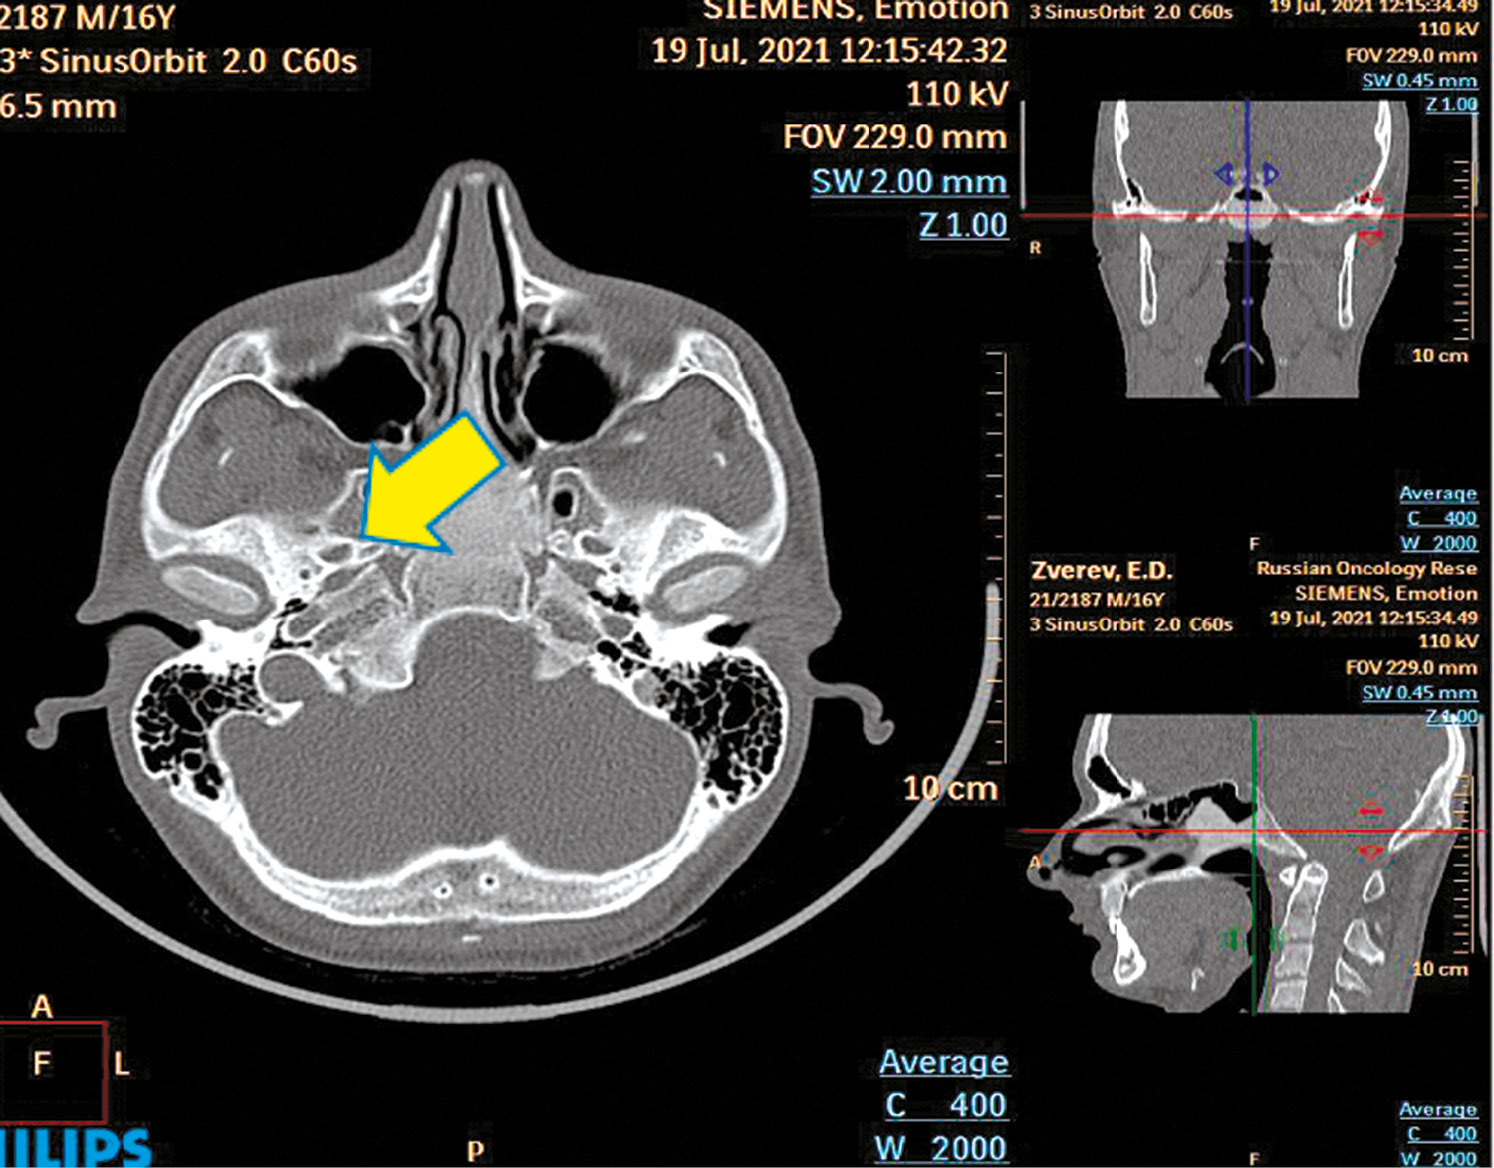

На компьютерной томографии лицевого скелета с контрастированием видно, что в средних отделах основной пазухи определяется объёмное образование с достаточно ровными контурами костной плотности, неоднородной структуры в виде утолщения перегородки основной пазухи, клиновидного гребня, решетчатой кости. Контрастное вещество не накапливает, деструктивных и периостальных изменений в других костях черепа не выявлено. Размер образования 3,2×1,7×3,6 мм. РКТ-картина соответствует фиброзной дисплазии клиновидной кости (рис. 1).

Рис. 1. РКТ-картина фиброзной дисплазии клиновидной кости (опухоль основной пазухи, клиновидного гребня, решетчатой кости) / Fig. 1. RCT picture of fibrous dysplasia of the sphenoid bone (tumor of the main sinus, sphenoid crest, latticed bone)